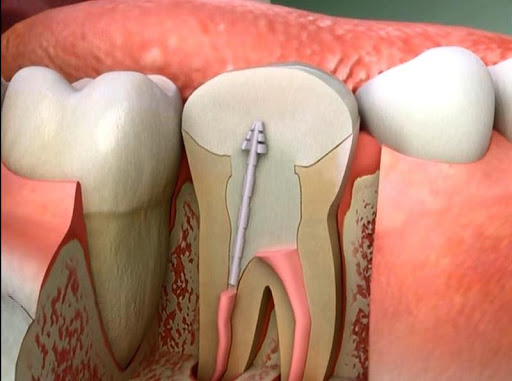

Bir sonraki adımda, enfeksiyonlu bölgeye ulaşmak için dişin içine bir delik açılır. Bakterilerle birlikte pulpa, çürümüş sinir dokusu ve bu bölge içerisindeki ilgili enfeksiyon döküntüleri dişten uzaklaştırılır. Temizleme işlemini tam olarak yapabilmek ve kanalı etkin bir şekilde doldurabilmek için kanalın genişletilmesi gerekir.

Kanal genişletilmesi için tırnak törpüsüne benzeyen kanal aletleri kullanılır. Bu işleme kanal eğeleme denir. Bu işlem sırasında artık sinirler alındığı için hasta hiçbir ağrı hissetmez. Hem eğeleme işlemi esnasında biriken döküntüleri hem de içeride kalan kalıntıları temizlemek için, su veya sodyum hipoklorit bileşenleri periyodik olarak kullanılır.

Dişin içi tamamen temizlendikten sonra bu boşluğun doldurulması, hem yeni enfeksiyonları önlemek hem de dişe mukavemet kazandırmak açısından önemlidir. Dişin içini doldurmak için, guta percha adı verilen bir kauçuk bileşiği kullanılır. Guta percha ince bir çubuğa benzeyen fakat vücutta reaksiyona yol açmayan bir maddedir. Bu madde yerleştirilmeden önce diş kanalının kuruluğu kağıt konlarla sağlanır ve açılan kanalların uzunluğu özel aletle ölçülür. Bu uzunluğa göre guta perchalar ayarlanır ve fazlalıklar ısı ile kesilir. Guta percha kök kanalının ana boşluğunu dolduran madde olsa da, sızıntıyı engellemek ve sabitlemek için ek karışımlar kullanılması gerekir. İşlem sonucunda açılan delik kapatılır ve kanal tedavisi tamamlanmış olur. Dişin hasarına bağlı olarak, bazı durumlarda dişin kronlanması ( kaplama yapılması) gerekebilir.